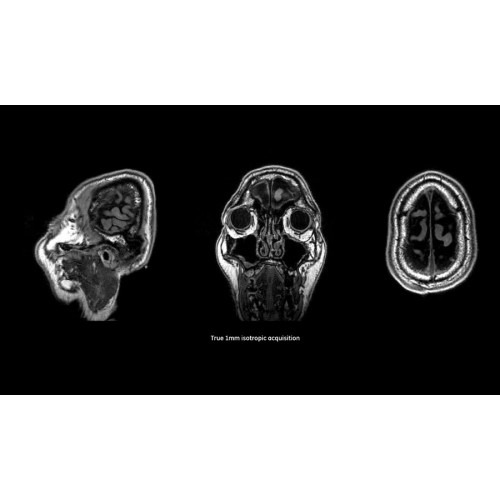

Система SIGNA Pioneer воплощает поразительные достижения в области визуализации. Передовая технология Total Digital Imaging (TDI) позволяет добиться большей четкости изображений и на четверть повысить соотношение сигнал/шум.

- Технология Direct Digital Interface (DDI) использует независимый аналого-цифровой преобразователь для оцифровки сигнала от каждого из 97 радиочастотных каналов, что обеспечивает значительное увеличение качества за счет уменьшения фонового шума.

- Технология Digital Micro Switching (DMS) — это следующее поколение технологий радиочастотных катушек, основанное на замене аналоговых схем блокировки сверхбыстрыми микропереключателями (MEMS), что делает возможным быстрое переключение катушек для дальнейшего расширения возможностей визуализации с нулевым TE.

- Технология Digital Surround Technology (DST) — это новая технология объемной оцифровки данных, объединяющая сигналы от каждого элемента катушки. Прекрасное соотношение сигнал/шум и чувствительность поверхностных катушек в сочетании с превосходной однородностью и высокой проникающей способностью встроенной радиочастотной катушки — все это позволяет создавать качественные изображения не только позвоночника, но и всего тела.

Помимо технологии 97 РЧ-каналов, SIGNA Pioneer использует магнит 3.0Т высокой однородности, предназначенный для повышения качества визуализации во всех областях, а также закладывающий прочный фундамент для долгосрочных инвестиций и роста клинических возможностей.